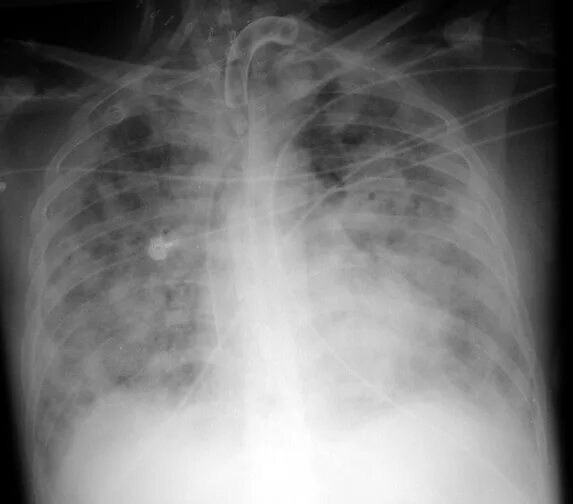

Ордс крипта